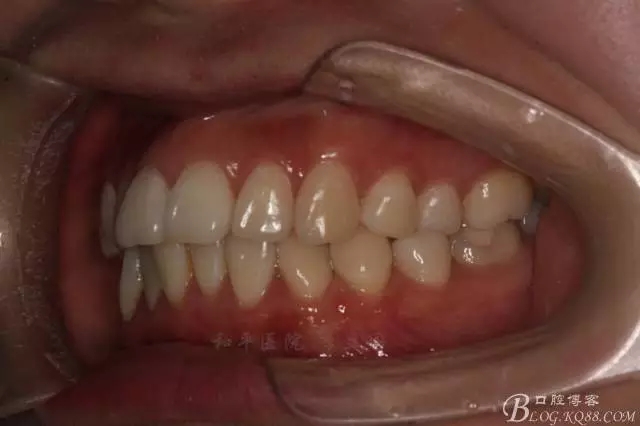

患者,女,主訴:牙齒不齊。

如圖,該病例為簡單排齊病例,但77鎖合是矯治中的關(guān)鍵所在,你會(huì)怎么處理?

該病例主要為17、27頰側(cè)位同時(shí)伴有伸長,當(dāng)然種植支抗可以解決,但還有簡單實(shí)用的辦法嗎?如圖,在橫腭桿遠(yuǎn)中延伸出牽引鉤,位置盡量遠(yuǎn)離合平面,7粘舌側(cè)扣,牽引力的方向?yàn)閴旱图吧嘞?,下圖為兩個(gè)月的效果,17已到位,27還未到位。